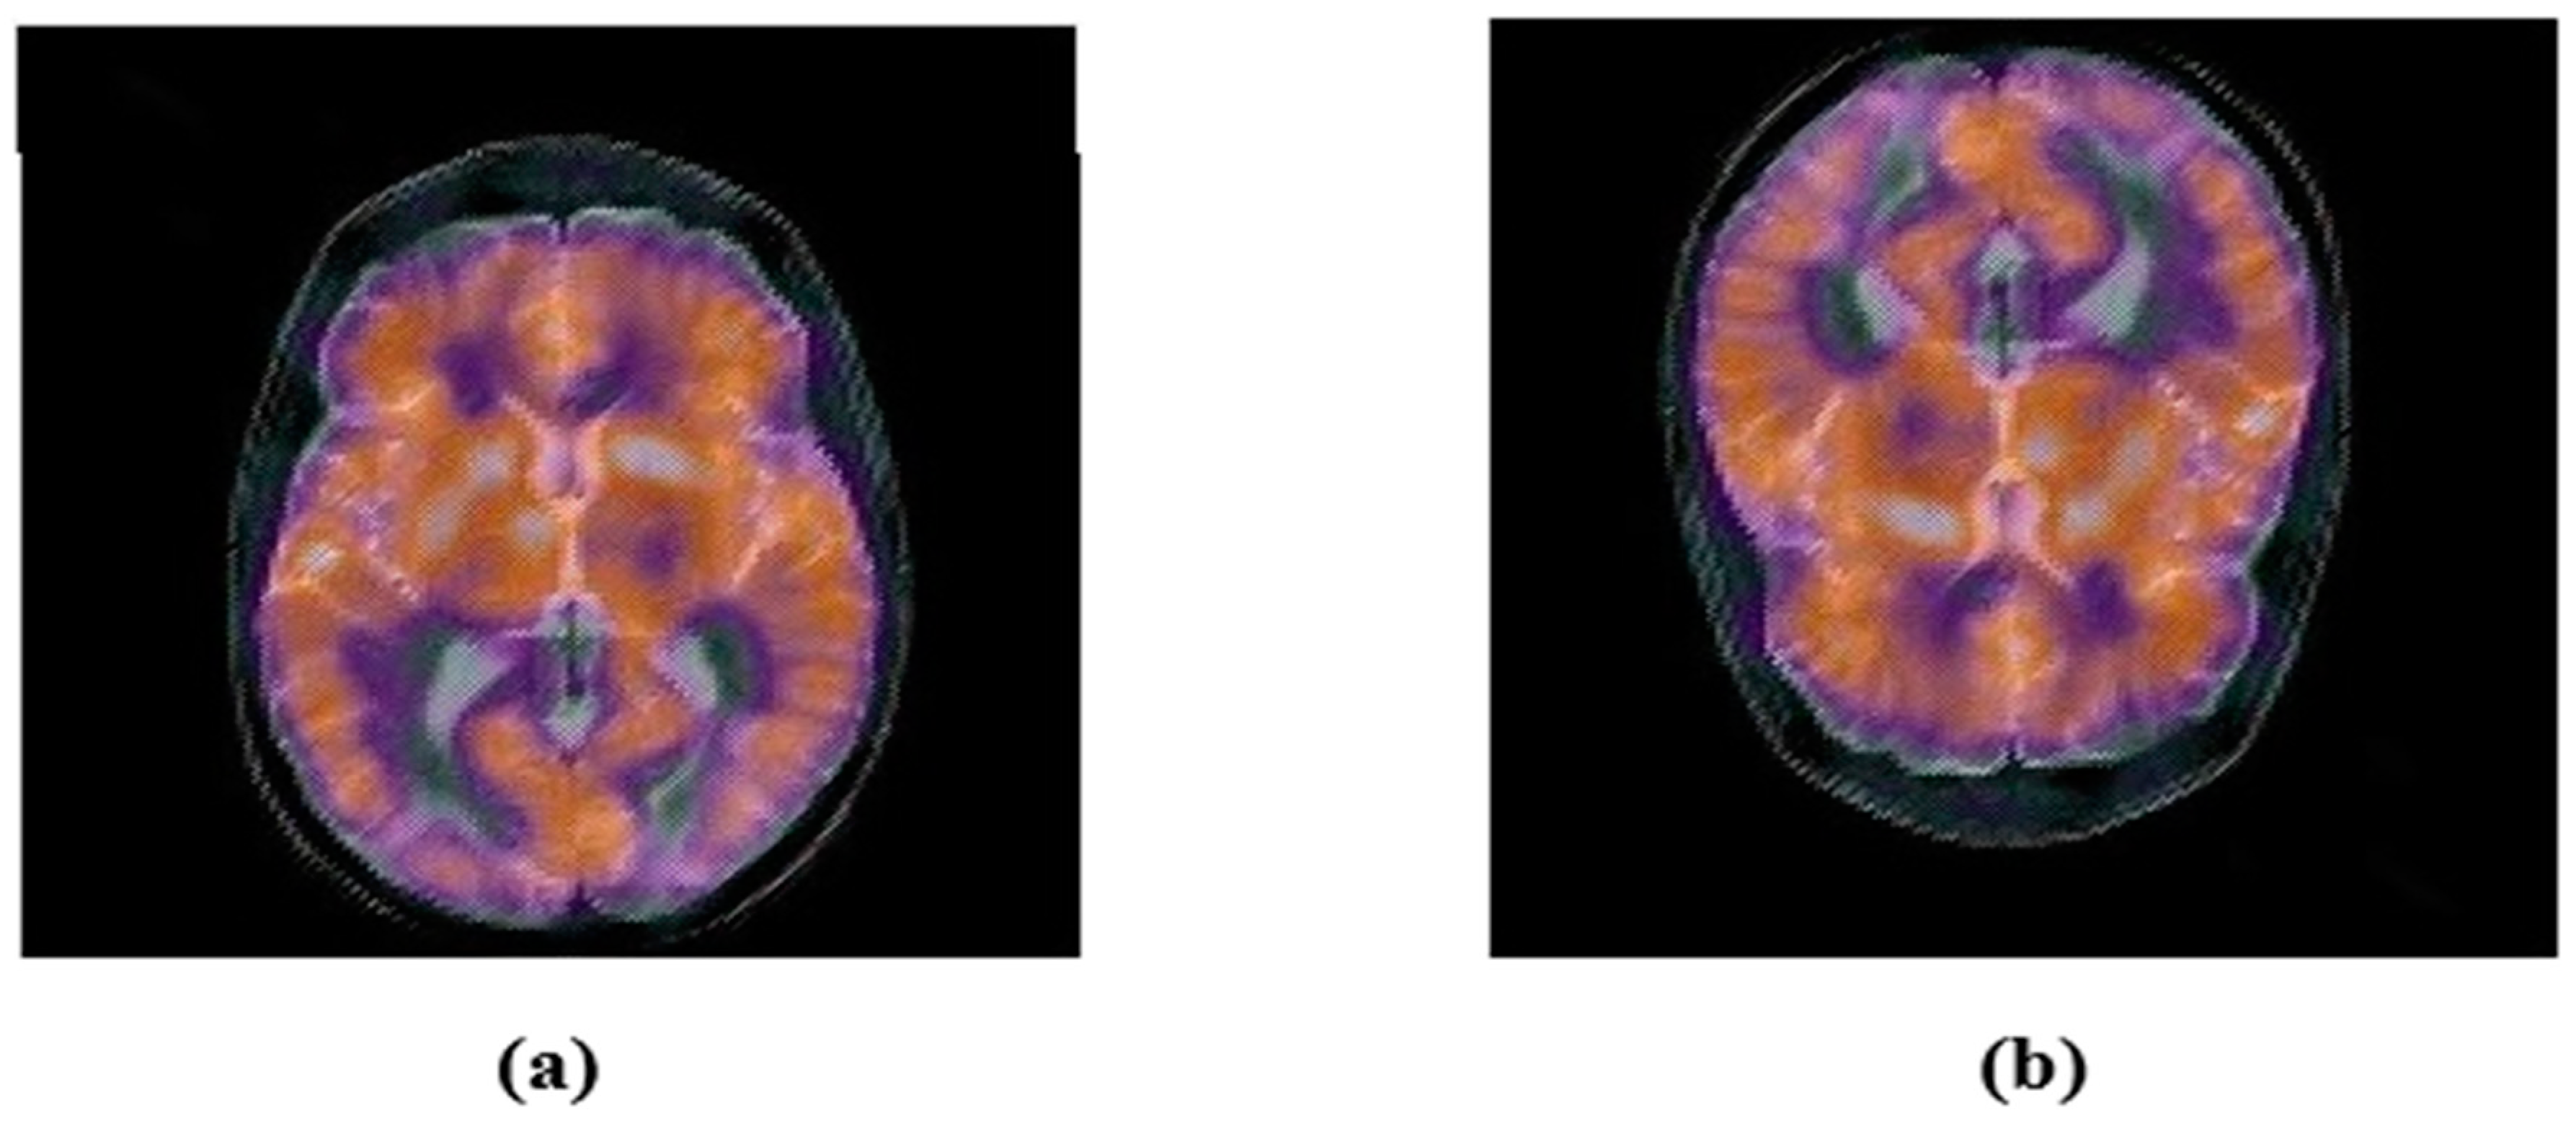

4.2.2. Geometric Attacks

| Applied Attack | LWR (1.0, 0.75) | LWR (0.5, 1.0) | Horizontal-flipping | Vertical- Flipping |

| Extracted watermark | ![]() | ![]() | ![]() | ![]() |

| BER | 0.0049 | 0.0068 | 0.0010 | 0.0010 |

| NC | 0.9892 | 0.9849 | 0.9979 | 0.9979 |